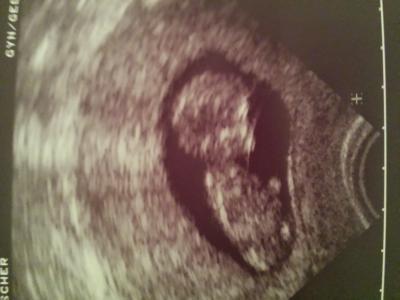

Ich durfte nach 6 langen Wochen endlich wieder zum Doc...freu!!!! Es sah alles super gut aus....unser Muckelchen sah so süß aus....mir kamen sofort die Tränen...schnief....es hatte wahrscheinlich gerade seine Turnstunde, es war wie verückt am Zappeln...hihi.....Gestern war ich bei 11+5 ssw und es bleibt beim 8.05.2014!!!! Nun heißt es bis zum 05.11 warten und dann wird die Nackenfalten messung gemacht!!!! Sorry Mädels das ich in letzte Zeit nicht bei euch war...aber mein Handy war kaputt....jetzt hab ich ein neues Handy und bin wieder täglich on:) An alle die leider unseren Bus verlassen mussten wünsche ich viel Kraft und alles gute!!!! So nun heißt es: fest Anschnallen und eine sichere Fahrt in den Mai 2014:))))

Nabend, Das ist super das alles in bester Ordnung ist. Ich finde es auch immerspannend zu sehen,wie sie so turnen und man merkt noch gar nichts davon:-) Ich muss noch 3 Wochen warten. Dann sehen wir unseren Krümel hoffentlich auch turnen Ich war gestern außerplanmäßig beim Doc, da ich so tierische Krämpfe nachts im Unterleib hatte. Aber zum Glück ohne Blutungen. Bin dann doch zur Sicherheit los und er konnte mich beruhigen. Der Krümel ist gut gewachsen 2,4cm und hat gut geschlagen. Waren wohl doch schon die Mutterbänder und mein Bauch ist auch zuvor schon ganz schön gewachsen. Hoffe jetzt wird alles gut sein bi zum nä Termin.:-):- Lg Daniela Im Anhang ein Bild von unserem noch Böhnchen:-)